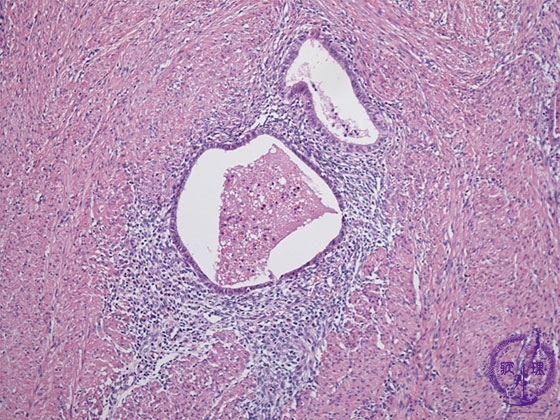

- ★(2)Adenomyosis

Histology (HE stain, intermediate power): Endometrial tissue consisting of endometrial glands and stromal cells in the myometrium.